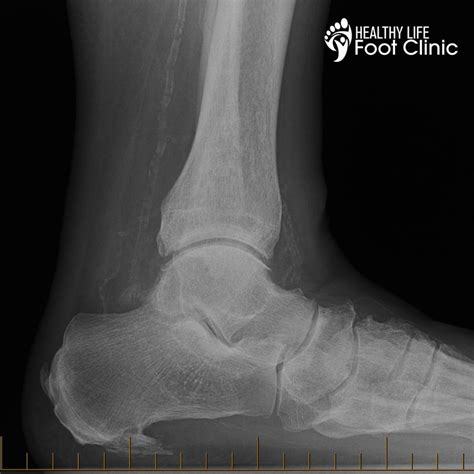

A heel spur is a calcium deposit, or bony protrusion, that develops on the underside of the heel bone. Over a period of several months, these bony growths develop. They are often associated with plantar fasciitis—the inflammation of the fibrous band of connective tissue (the plantar fascia) that runs along the bottom of your foot and connects your heel bone to the ball of your foot. It is important to note that the spur itself is often not the direct cause of pain; rather, it is the inflammation of the surrounding tissue that leads to the debilitating symptoms.

Visual Appearance Visible on X-ray Not visible on X-ray

While home remedies are often effective, there are times when medical intervention is necessary. If your heel spur symptoms persist for more than a few weeks despite rest and home care, it is time to visit a podiatrist. They may suggest more advanced treatments such as cortisone injections, physical therapy, or, in rare cases, surgical options. Diagnostic imaging, such as an X-ray, is usually the gold standard for confirming that a bony spur is indeed the source of the discomfort, ensuring you receive a targeted treatment plan.